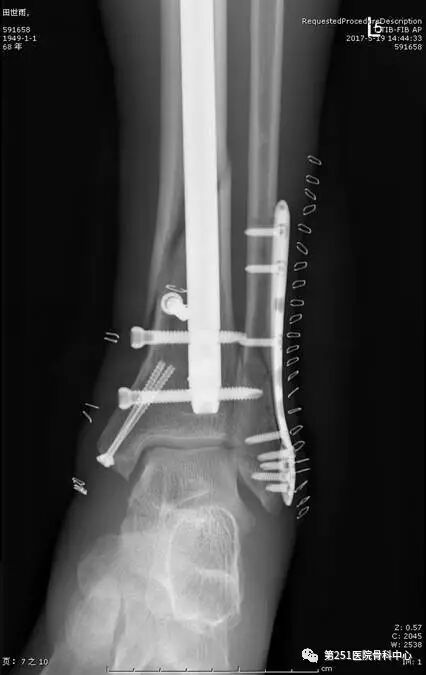

病例9:男性、68岁、车祸伤,胫腓骨远端骨折。

![]()